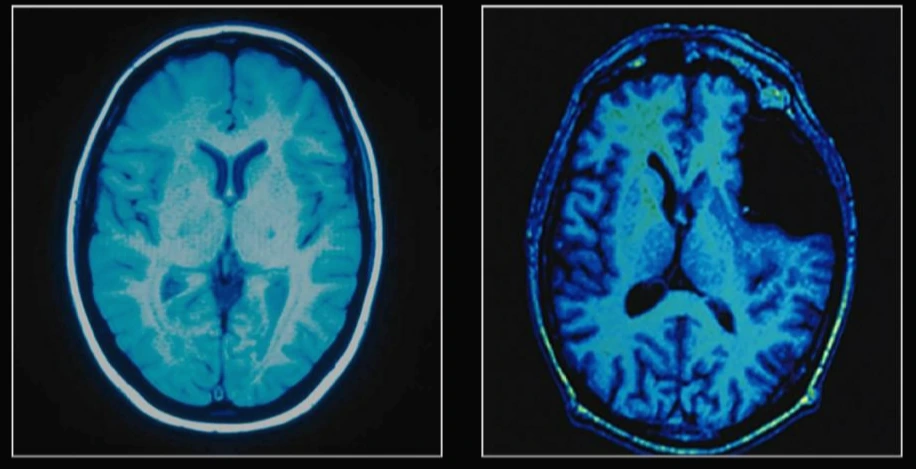

일반인의 뇌(왼쪽)와 Weinstein의 뇌(오른쪽)

Weinstein의 뇌는 일반인의 뇌와 약간 다른 점이 있습니다. 오른쪽 사진의 윗부분 뇌가 비어 있는 게 보이시나요? 그는 오랜 기간 뇌에 생긴 혹(낭종)으로 고통받아 왔습니다. 이 혹이 뇌를 손상시켜 지금의 뇌 상태를 만든 것이죠.